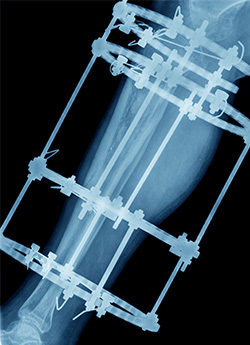

Esta operación consiste en colocar al paciente un fijador externo que se une a la extremidad afectada por medio de agujas percutáneas (especie de pernos). La cirugía puede ser con anestesia regional (epidural) o general y dura aproximadamente tres horas. La hospitalización es de alrededor de cinco días.

Luego, diariamente, el paciente debe ir alargando milimétricamente el fijador para que la extremidad se vaya adaptando a este proceso. El tiempo que la persona debe permanecer con estos dispositivos depende del segmento corporal involucrado (pierna, muslo, brazo) y de cuántos centímetros es necesario alargar, pero en general toma un promedio de tres meses, tiempo durante el que también se debe realizar kinesiterapia.